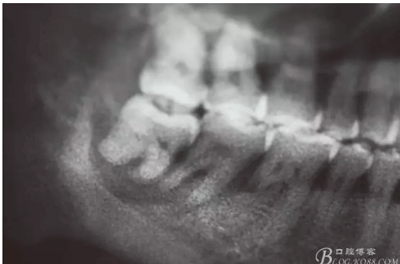

圖2.局部的放大影像情況。48骨質(zhì)吸收至下頜管邊緣,陰影范圍廣,拔除48后牙槽窩處理要小心。